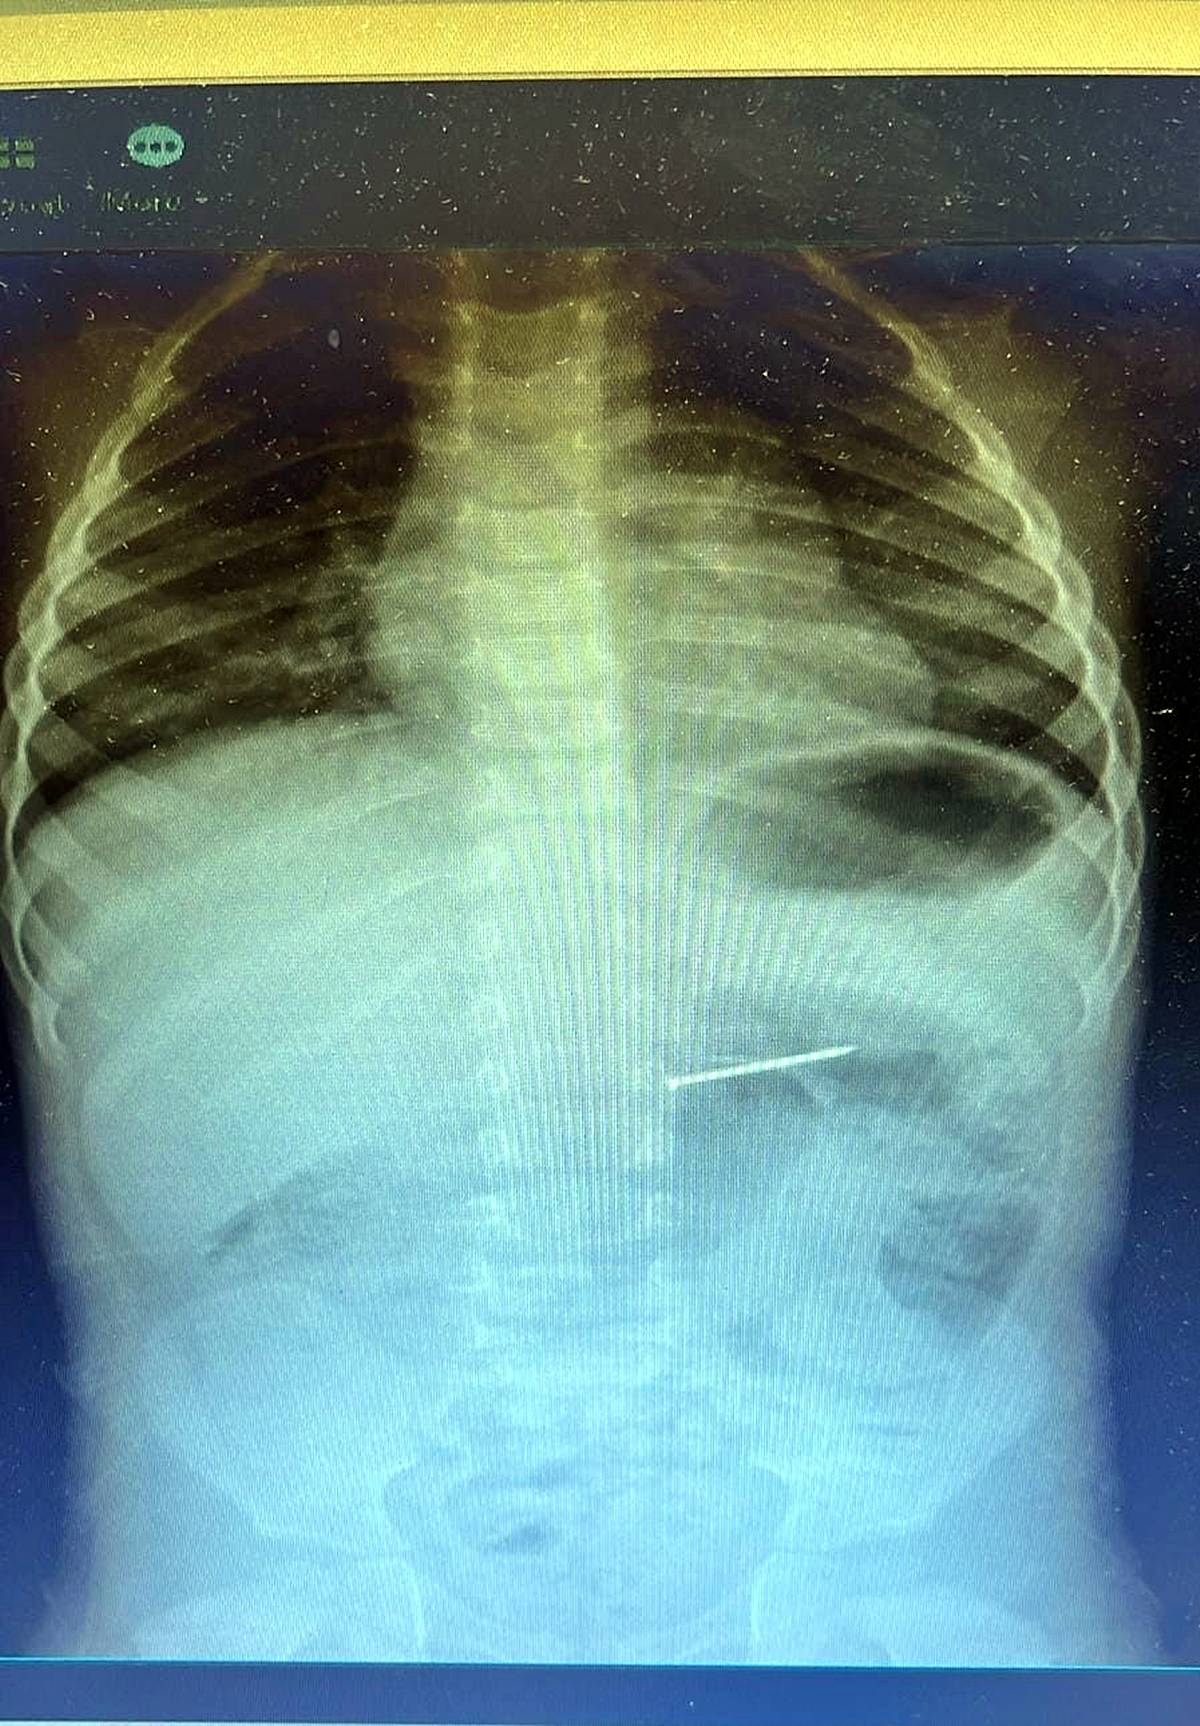

Yapılan radyolojik incelemeler sonucunda, yaklaşık 4 santimetre uzunluğundaki çivinin çocuğun midesinde olduğu tespit edildi.

Bu kritik durum karşısında hızla endoskopik müdahale kararı alındı. Başarılı bir operasyonla çivi, çocuğun sindirim sistemine herhangi bir zarar vermeden mideden çıkarıldı.